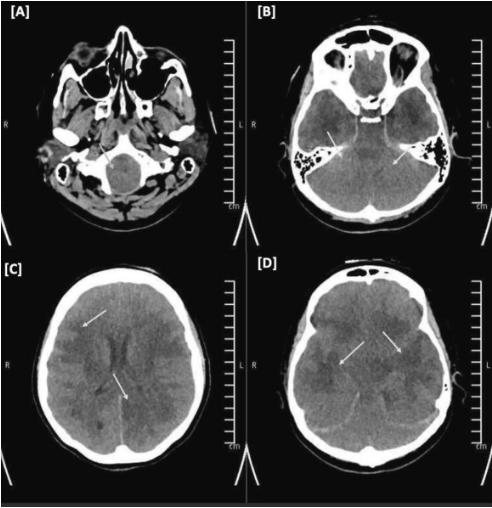

图3、头部CT无对比增强

入院第4天,尽管接受了5天的静脉注射类固醇、严格调节的渗透治疗和镇静治疗,脑水肿的进展是不可避免的,随访的CT头(图3)显示弥漫性脑水肿的间隔明显增加,并扩展到脑干,肿块效应的间隔增加,更多的心室系统消失和扁桃体疝。